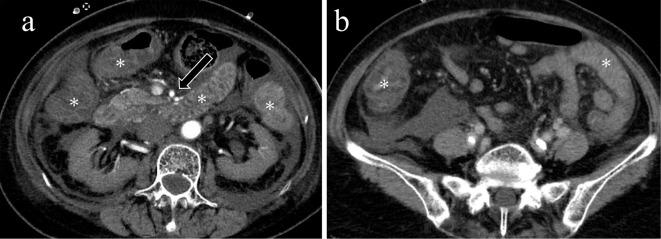

Acute mesenteric ischemia is a life-threatening condition. A comprehensive approach involving a multidisciplinary team to review patient background, clinical history, physical examination, laboratory data, and imaging examination for respective diagnosis of superior mesenteric arterial occlusion, nonocclusive mesenteric ischemia, and superior mesenteric venous occlusion is essential. The most important imaging modality is computed tomography, which is used for diagnosis and for directing therapeutic strategy (e.g., endovascular revascularization, surgical bowel resection, or conservative management). Computed tomography image findings can support triaging of irreversible transmural bowel necrosis compared with reversible ischemic change with reperfusion. In this review article, the computed tomography imaging findings specifically associated with the pathophysiology of superior mesenteric arterial occlusion, nonocclusive mesenteric ischemia, and superior mesenteric venous occlusion are reviewed.

急性肠系膜缺血是一种危及生命的疾病。采用多学科团队的综合方法来审查患者背景、临床病史、体格检查、实验室数据以及影像学检查,以分别诊断肠系膜上动脉闭塞、非闭塞性肠系膜缺血和肠系膜上静脉闭塞至关重要。最重要的影像学检查方法是计算机断层扫描,它用于诊断并指导治疗策略(如血管内血运重建、手术肠切除或保守治疗)。计算机断层扫描图像结果有助于区分不可逆的透壁性肠坏死与可通过再灌注逆转的缺血性改变。在这篇综述文章中,将对与肠系膜上动脉闭塞、非闭塞性肠系膜缺血和肠系膜上静脉闭塞的病理生理学具体相关的计算机断层扫描影像学结果进行综述。